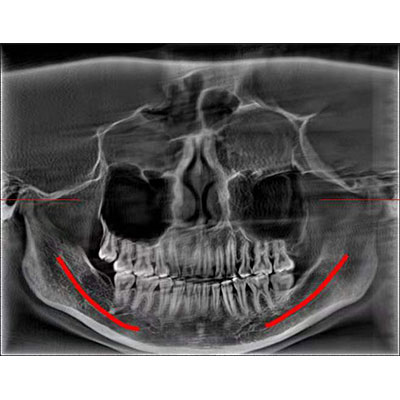

該款牙科CBCT產(chǎn)品采用動態(tài)平板探測器,獲得三維圖像的同時還具有數(shù)字化全景功能,廣泛應用于口腔頜面外科、正畸科、正頜外科、種植科、牙體科、顳下頜關節(jié)科等術前術后。

通過三維容積影像,提取高清口腔全景影像。

專有圖像校正技術,去除金屬偽影,提高圖像分辨率。